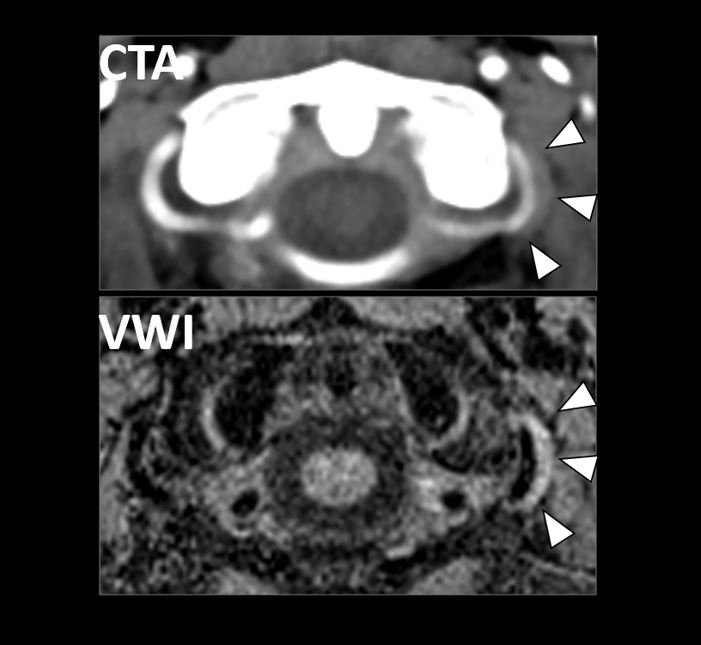

Vessel Wall Imaging of a Carotid Web (May 2022)

We report imaging findings on CTA and VWI of a carotid web that was the most likely cause of ischemic stroke.